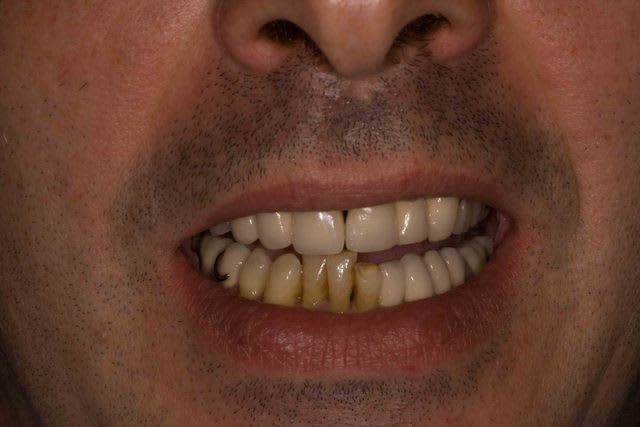

Maintenant il les trouve jaunes et veux les blanchir. Comme quoi un nouveau sourire amene souvent un nouveau regard.

Le probleme c'est que maintenant il ne les trouvent pas belles et veut les blanchir/meuler... Sont jamais content les patients.

C'est les dent 31-41-42-43 qui sont jaunes au max, c'est pas les courones qui sont blanches !

Chez nous, c'est pas blanc ça !

Je ne comprenais pas le plan de tx de 31 à 43...mais si c'est le patient qui décide...

Céramique : A l'orgine le patient n'en avait strictement rien a foutre de l'esthetique . Laisser ces 4 dents saines , meme jaunes, n'empechait pas de réaliser tout le reste . Alors si le patient le veut et que je peux il n'y avait aucune raison de toucher a ces dents (sauf peut etre pour les canadiens :) ).